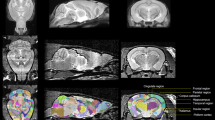

Irradiation

During the administration of radiation, the rats were anesthetized with 3.6% chloral hydrate (360 mg/kg), and the control rats were treated similarly. The rats were placed in a prone position in a linear accelerator (SL 18, Philips, UK) as described previously [14, 15]. Each rat received a single dose of 0 Gy or 10 Gy of 4 MeV electron beam cranial irradiation.

Impaired hippocampus-dependent behaviors in young rats after cranial irradiation

Learning and memory tasks were performed in young rats to evaluate cognitive dysfunction 1 and 3 months following cranial radiation. One month after irradiation, there was no significant difference in the place navigation and the spatial probe test (data not shown) between the two groups. However, the control rats found the platform faster than the 3-month postirradiation rats (Fig. 1A). All rats improved their performance on days 1–4 during the place navigation test, while on day 5, the radiation group had a longer latency time than the control (25.59 ± 3.27 s vs. 15.98 ± 2.01 s; n = 15–20, p = 0.013; Fig. 1B). In the spatial probe test, the control rats spent significantly more time in the target quadrant compared to the treated rats (27.75 ± 1.27% vs. 21.95 ± 1.50%; n = 20, p = 0.002; Fig. 1C). The control rats crossed the target annulus nearly four times, whereas the irradiated rats crossed only twice (Fig. 1D).

Cranial irradiation-induced cognitive deficits in young rats. A The swim tracks of the rats during Morris water maze testing. B Comparison of the latency to find the platform between the control and irradiated groups. C The percentage of target quadrant exploring time between the two groups in probe test. D Number of crossings in the original location of the platform. E Diagram of the object recognition task. F The times spent exploring a novel object is shown as a ratio of the total times at 1 month after irradiation

A novel object recognition test was used to evaluate hippocampus-dependent nonspatial learning and memory (Fig. 1E). During the 3-min training session, sham and radiated rats showed no significant difference in exploration time of the objects (data not shown). One hour after the training trial, rats were tested for novel object recognition. Sham rats spent more time exploring the novel object than the familiar object at 1 month after 10 Gy (control: 58.19 ± 1.33%, irradiated: 47.51 ± 4.15%; n = 20, p = 0.035; Fig. 1F), but there were no group differences at 3 months postirradiation (p > 0.05; not shown).